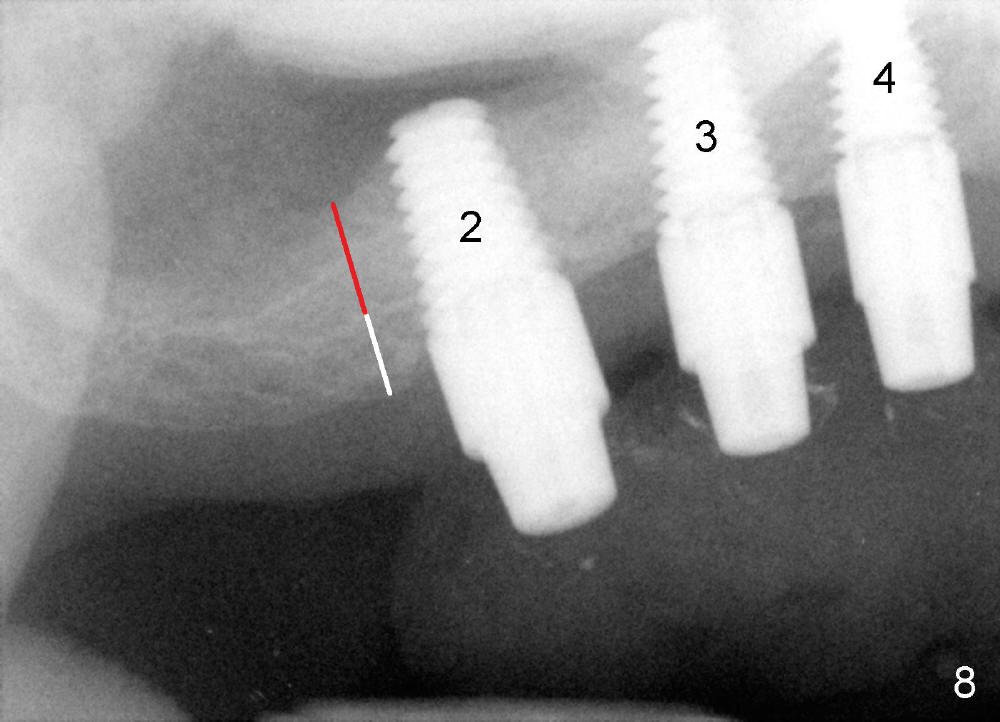

Three months postop, new bone appears to form (Fig.8 red line) on the top of the existing bone (white line). The vertical PA taken at the same time (Fig.9) shows bone formation around the other implants.